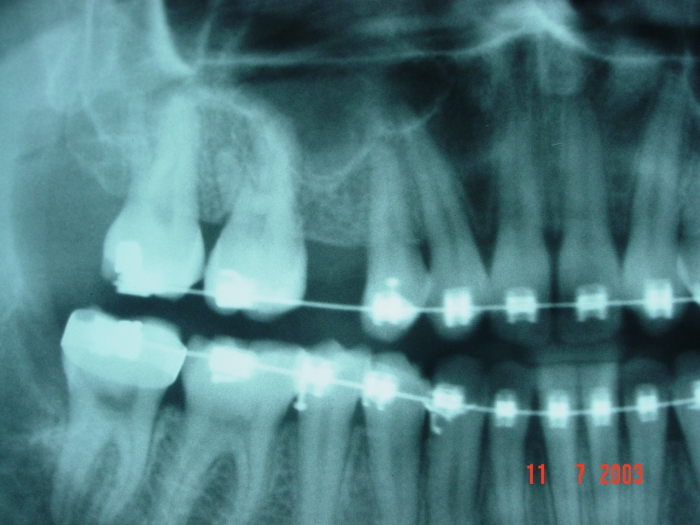

Imagem Final do caso terminado em dezembro de 2004.